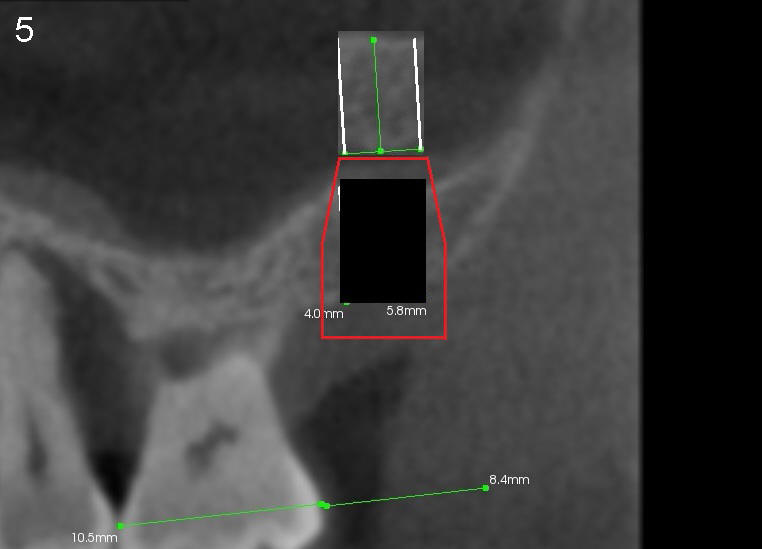

A trephine bur with outside diameter 4 mm will be used to create osteotomy and harvest the bone core (Fig.3; white lines). If the bone does not come out with the trephine bur, it will be pushed upward slowly and gently with a flat end osteotome or tap (Fig.4). When an implant is placed (Fig.5 red outline; 6x11 mm), it is covered by the vital bone above with blood supply coming from the sinus membrane.

Fig.7,8 are CT coronal sections, showing #2 ridge morphology and implant design, respectively.